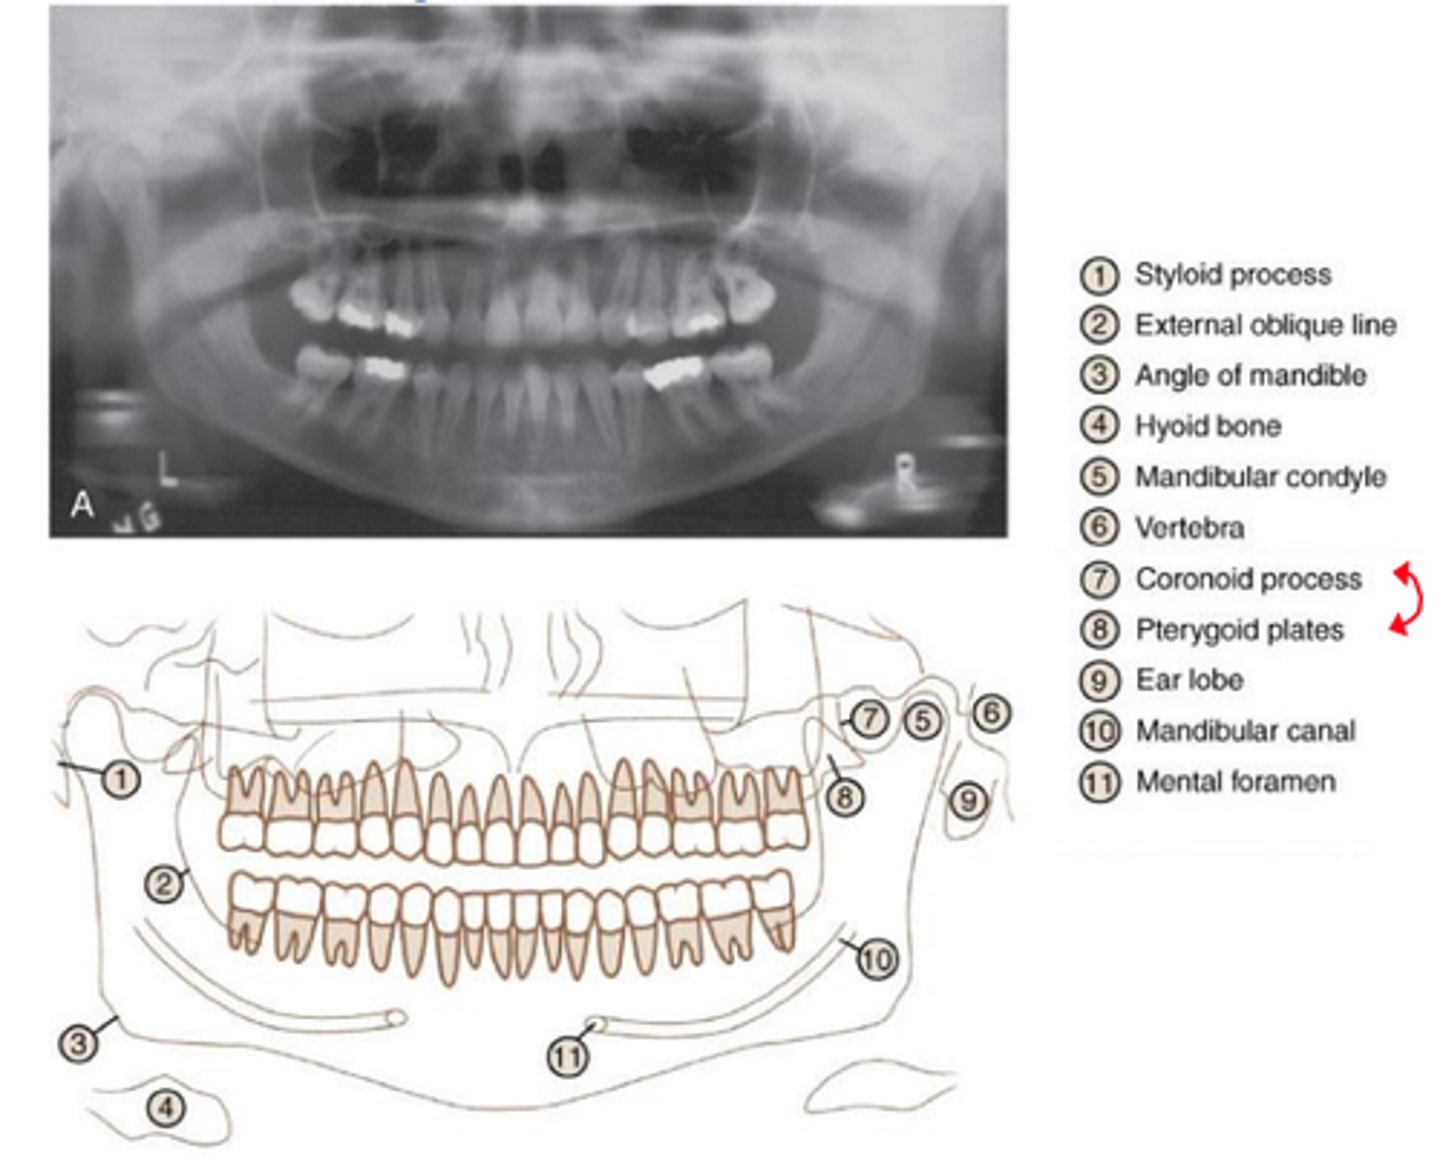

panoramic radiograph

provides full view of the upper & lower jaw

panoramic radiograph purpose

allows us view your head, neck, & jaw, & how they work together as a whole

which of the following landmarks useful when mounting images of the mandibular posterior area?

mental foramen

which of the following landmarks is useful when mounting images in the maxillary posterior area?

floor of the maxillary sinus